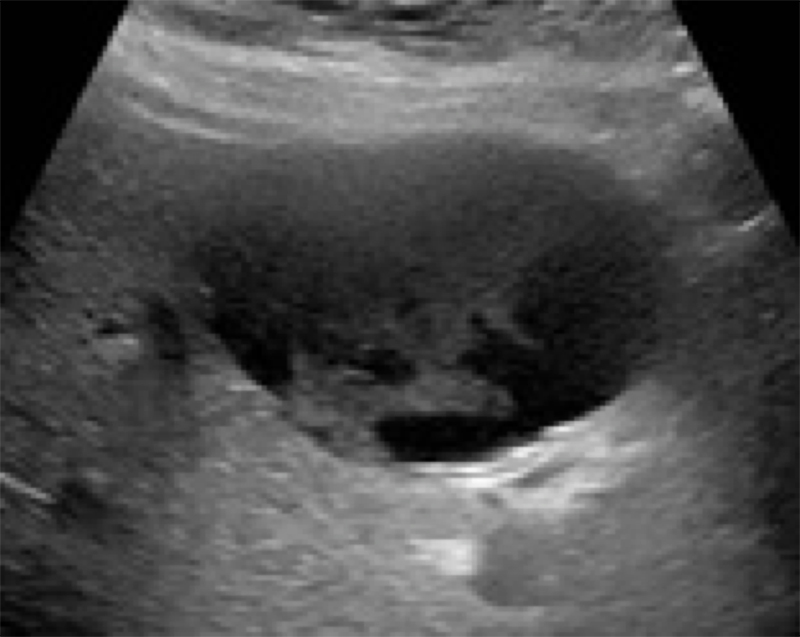

Figure 24A. Large pyogenic liver abscess with heterogenous material swirling inside the lesion, and “dirty shadowing.”

Figures 24B & 24C. Large pyogenic liver abscess with heterogenous material swirling inside the lesion, measuring >11cm in the long dimension (B) and >5cm in the shorter dimension (C).